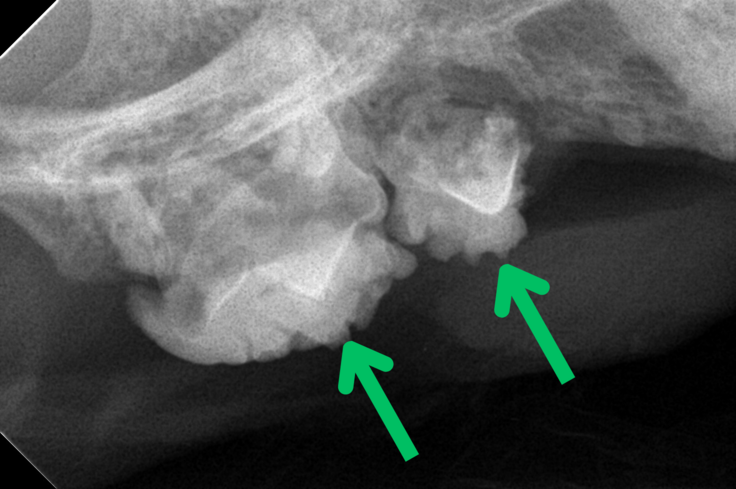

最近では、口臭と出血があり、ごはんも満足に食べられない状態の猫さんが保護されました。診察の結果、重度の歯周病で、歯科レントゲンでは歯根がすでに溶けていることが確認されたため、全臼歯抜歯の処置を行いました。

【写真:歯周病の口の様子(緑矢印は歯が歯石で覆われている)】

【歯科レントゲン写真:歯根が溶けるほどの歯周病が判明】